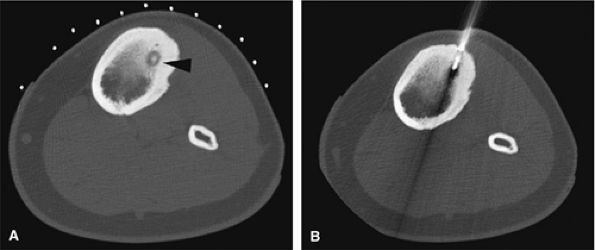

![]() |

FIGURE 14-10 ● Axial graphic illustration shows radiofrequency ablation of an osteoid osteoma. Nidus is shown in red with surrounding cortical thickening. The radiofrequency probe is positioned within the nidus.

FIGURE 14-11 ● (A) CT images from a radiofrequency ablation show osteoid osteoma nidus in the anterior tibia (arrowhead) with surrounding cortical thickening. (B) Radiofrequency probe is positioned within the nidus for treatment.